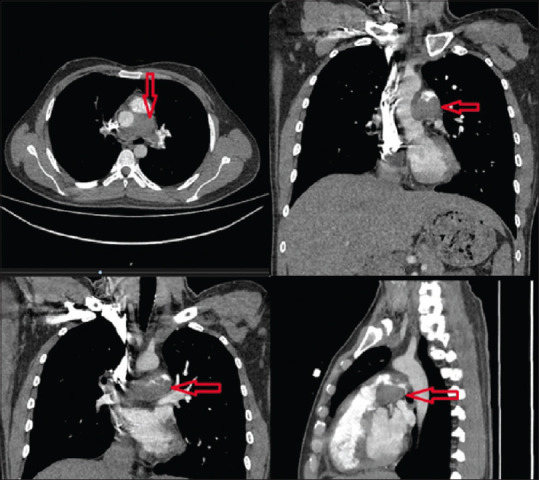

在急诊科,患者会出现很多症状。其中一个主要症状就是发烧,这可能是唯一的症状,我们的病人就是如此。不仅感染、药物、外伤等会引起发烧,就连未确定的癌症类型也会引起发烧。在本病例中,我们介绍了一名发热持续 3 周的 28 岁男性患者,入院诊断为肺动脉内膜肉瘤,一般被误认为是肺血栓栓塞症,以提高人们对这种致命癌症的认识。

In the emergency department, there are many symptoms patients present. One of the major symptoms is fever which could be the only symptom, as our patient had. Not only do infections, drugs, trauma, etc., cause fever, but also undetermined cancer types do. In this case, we are presenting a 28-year-old male coming with a 3-week duration of fever and being admitted with the diagnosis of pulmonary artery intimal sarcoma as generally misconceived with pulmonary thromboembolism, to raise awareness of this fatal cancer.